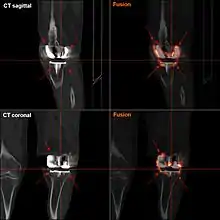

Components and zones

Standardized zones around the components are used for specifying, for example, signs of loosening on radiographic follow-up. There are various classification systems for specifying such zones,[44][45] including by KS (Knee Society) zones published in 2015.[43]

Specific KS zones are as follows, with * meaning that the zone can be specified as "A" (anterior), "P" (posterior), "M" (medial) or "L" (lateral):[43]

- Femoral component (lateral view)

- Zone 1 and 2: Anterior and posterior flange, respectively.

- Zone 3: Central box/distal fixation region, where "A" and "P" designate the respective chamfers if visible*

- Zone 4: Stem extension*

- Zone 5: Stem

- Tibial component:

- Zone 1: Anterior on lateral view, medial on anteroposterior (AP) view.

- Zone 2: Posterior on lateral view, lateral on AP view.

- Zone 3: Central keel/stem/peg fixation region*

- Zone 5: Inferior aspect of keel or stem

Loosening of the prosthesis can be indicated on X-ray by thin radiolucent spaces around the implant, or more obviously by implant displacement.[53]